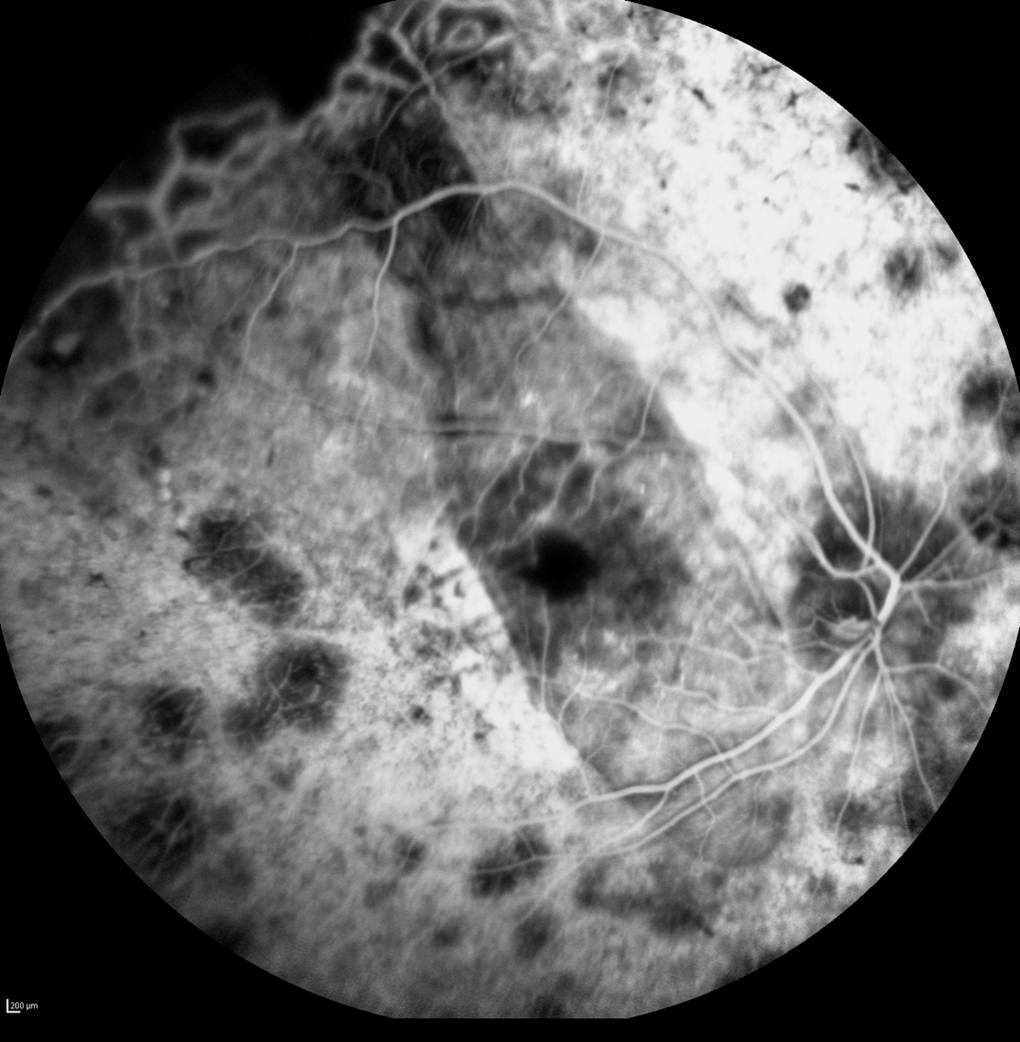

The subretinal microchip implantation involves placing a 1500-electrode microchip just below the retina, specifically in the macular region. Results of Retina Implant's first human clinical trial were published in the prestigious peer-reviewed journal Proceedings of the Royal Society B and showed placement of the implant below the retina, in the macular region, provided optimum visual results allowing patients to recognize foreign objects and to read letters to form words.